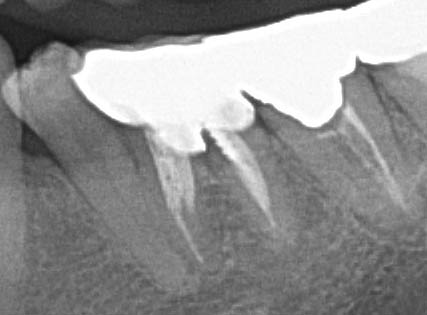

投稿日: 2025年12月16日 投稿者: 木田歯科医院根と根の間にむし歯があって残せない 根と根の間、根分岐部といいますがここに大きなむし歯があってこれは無理と判断しました。そもそも被せ物がしてあった歯なんですがここがトンネル状になっていてイヤな臭いがして気になっていたそうです。半分にセパレートして矯正で引き上げて小臼歯2本分にして残すという方法も無くは無いのかもしれませんがインプラントの方が予知性は高いと思います。